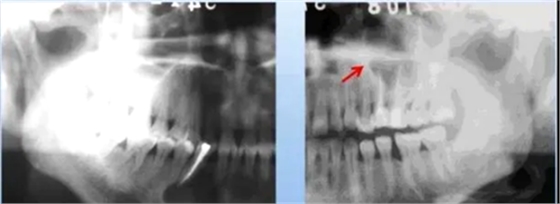

(3) 牙骨质结构不良

临床表现:好发于20岁以上女性,好发于下颌切牙的根尖部位。

X线表现:

早期:边界清楚、累及多个牙

第二期:骨质破坏区可见点状或团状钙化影

第三期:根尖区界限清楚、高致密度钙化影,牙周膜间隙及骨硬板清楚。